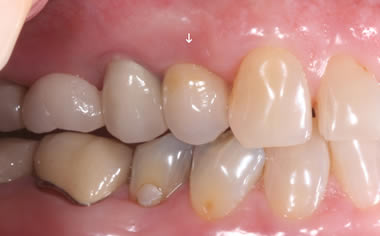

More back teeth replaced by dental implants

Case Five (4 images)